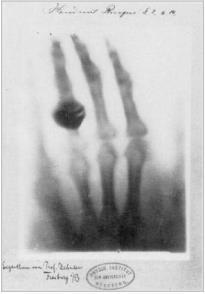

Foi ao final do século XIX que o físico alemão Wilhelm Conrad Rontgen fez a descoberta experimental dos raios-X após anos de pesquisas e trabalhos em laboratório e academia. (PEREIRA, 2012)

Segundo Francisco et al (2005), Roentgen, ao realizar experimentos com tudo de raios catódicos envoltos em cartolina preta notou a luminescência verde em uma tela de platinocianeto de bário que estava em seu laboratório. Ao incidir os raios sobre a tela interpondo diversos objetos, percebeu que muitos deles não alteravam a luminescência da tela, exceto chumbo e platina, que barravam totalmente.

Acidentalmente, ao segurar os materiais entre o tubo e a tela viu os ossos de sua mão envoltos das partes moles do membro. (FRANCISCO et al., 2005; PEREIRA, 2012)

Com a descoberta, Rontgen mergulhou por semanas em experiências a fim de determinar a natureza dos raios descobertos. Durante este tempo, trabalhou isolado no laboratório de sua casa e mantendo seu trabalho em segredo até ter certeza da validade das observações.

Durante seus experimentos meticulosos, trocou a tela luminescente por uma chapa fotográfica e convenceu sua esposa a ajudá-lo expondo a mão dela por certa de 15 minutos entre o tudo e a placa fotográfica, no meio do trajeto dos raios, o que causou o aparecimento de uma imagem com sombras mais escuras mostrando os ossos da mão e de um anel que sua esposa usava, cercado pela

penumbra dos tecidos do entorno caracterizados por uma sombra mais fraca. Este foi o primeiro “rontgenograma”. (FRANCISCO et al., 2005; PEREIRA, 2012)

O físico alemão mostrou que os “novos raios” descobertos, assim como a luz, podiam impressionar chapas, propagar-se em linha reta, entretanto, não eram refletidos nem refratados, tinham a capacidade de atravessas muitos corpos opacos à luz. A estes raios deu o nome de “raios-X”, também chamados de “raios Rontgen”.

Não demorou muito para que a notícia da descoberta rodasse o mundo. Em 1896, durante uma palestra, após explanar teoricamente seus experimentos, radiografou a mão do famoso anatomista Albert Bom Kolliker. Os jornais publicavam notícias fervorosas que diziam “A luz nova vê os ossos através da carne”. (FRANCISCO et al., 2005)

Conforme conta a publicação da Revista Imagem (Francisco et al., 2005), Rontgen foi procurado por muitas empresas para que suas novas descobertas fossem exploradas comercialmente, mas ele se manteve firme na tradição de professor universitário que acreditava que as descobertas e invenções pertenciam à humanidade para livre uso, sem controle de patentes e licenças. Foi com essa motivação que enviou ao British Medical Journal uma radiografia de um braço fraturado para provar avançado poder diagnóstico da sua descoberta.

A utilização dos raios X como método diagnóstico foi sendo aplicado em diversas partes do mundo, inclusive no Brasil, onde em 1896 foi apresentada à Faculdade de Medicina do Rio de Janeiro a primeira tese sobre o uso nos novos raios. Dessa forma, surgiram os pioneiros radiológicos, precursores da medicina radiológica. Com a popularização dos exames de raios X, surgem as primeiras instalações permanentes de laboratórios de radiografia em hospitais, criando a necessidade de médicos e técnicos especializados.

Figura 4 - Laboratório de Rontgen na Universidade de Wurzburg em 1895 e a mão radiografada da esposa de Rontgen também de 1895 Fonte: Mould, 1995 apud Pereira, 2012, p. 14

Pela sua descoberta Rontgen recebeu o prêmio Nobel de Física em 1901. E foi a partir desta data que o mundo começou a desconfiar do risco de exposição aos novos raios, com o surgimento de várias notícias de efeitos adversos (vermelhidão, depilação, infecção, descamação), necroses, amputações e mortes relacionadas aos raios X (FRANCISCO et al., 2005; PEREIRA, 2012)